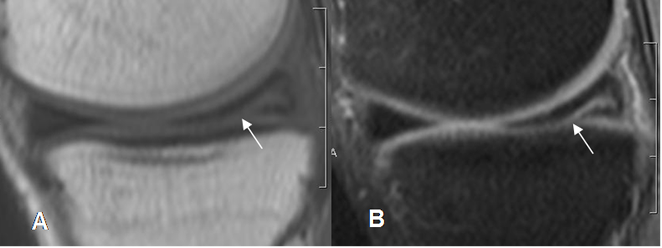

Fig 74. Ruptura meniscal oblicua.

A: RM sagital en T1 y B: RM sagital en STIR. Imagen en sentido oblicuo, que se comunica con la superficie articular inferior, por ruptura meniscal.